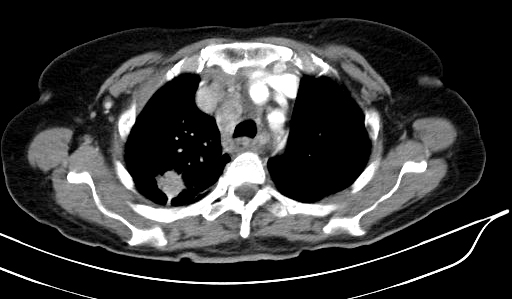

Metástasis intestinales yeyunales, forma de presentación de un carcinoma pulmonar

Los tumores primarios de intestino delgado son muy infrecuentes, siendo todavía más raros los metastásicos. Es excepcional que las metástasis de intestino delgado se manifiesten antes que el tumor primario. La presentación clínica puede requerir una resección quirúrgica intestinal motivada por perforación, hemorragia, obstrucción-suboclusión intestinal e incluso invaginación intestinal. La supervivencia, es escasa y generalmente no supera las 20 semanas, independientemente del tratamiento que se realice.